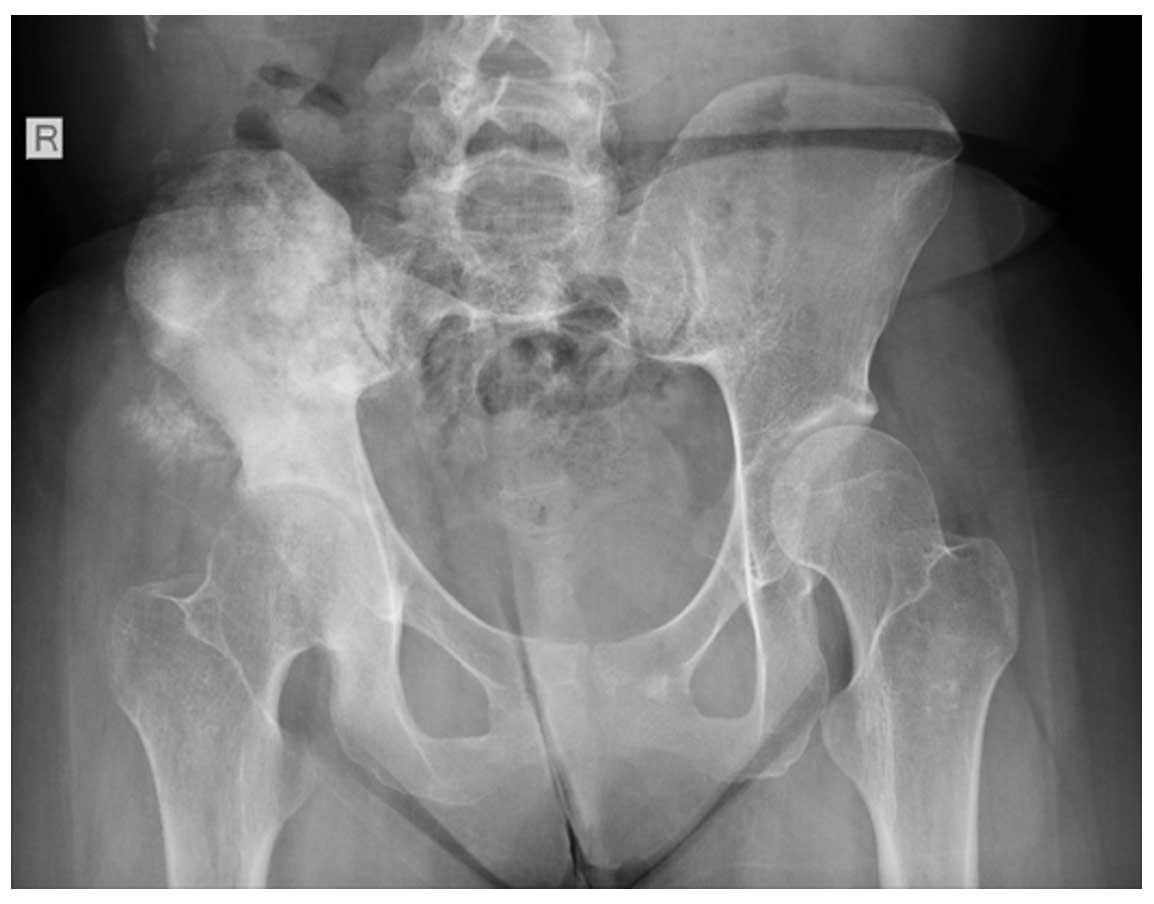

Ameliyat Öncesi: Röntgende sağ iliak kanatta skleroz, düzensizlik ve yumuşak doku içerisinde kitle dokusu görülmekte.